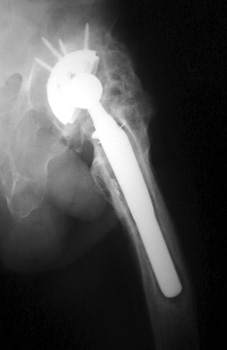

May be associated with pain and loss of range of motion.

HETEROTOPIC BONE FORMATION—Early heterotopic ossification (arrows) occurring 6 weeks after surgery